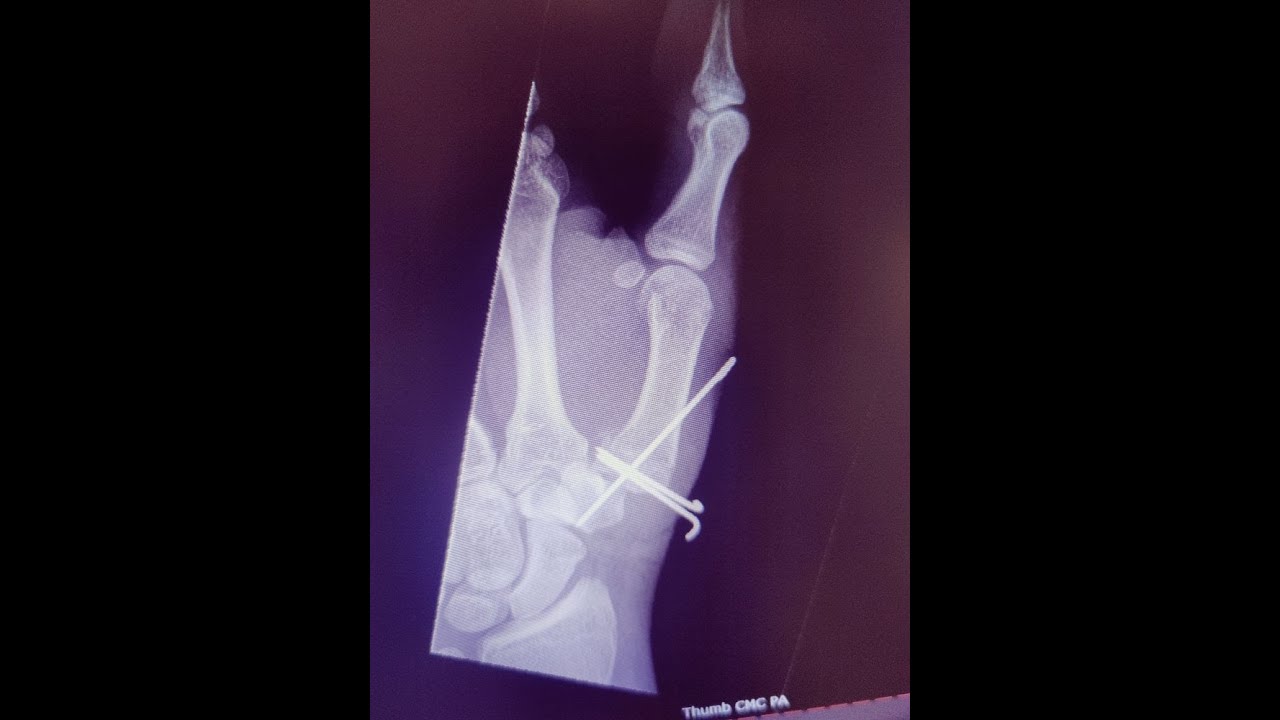

Closed Reduction and Pin Fixation of Hand FractureDislocation John Wrist Fracture Pin Removal Percutaneous pinning is a common procedure that we do to treat distal radius (wrist). What is a distal radius or wrist fracture? We have given you this factsheet because you have had an operation called an open reduction and internal fixation (orif) to fix the broken. Debride the pin sites in the operating. In case of pin loosening or pin. Wrist Fracture Pin Removal.

Wrist Fracture with Pin Repair Medical Stock Images Company Wrist Fracture Pin Removal Debride the pin sites in the operating. Intramedullary rods, pins, and other implants help bones to heal faster by holding things in place while the body heals. One of the common procedures to achieve this is ‘open reduction internal fixation’ (orif) surgery where the position of the broken bones is corrected and then held in place with a metal plate. Wrist Fracture Pin Removal.